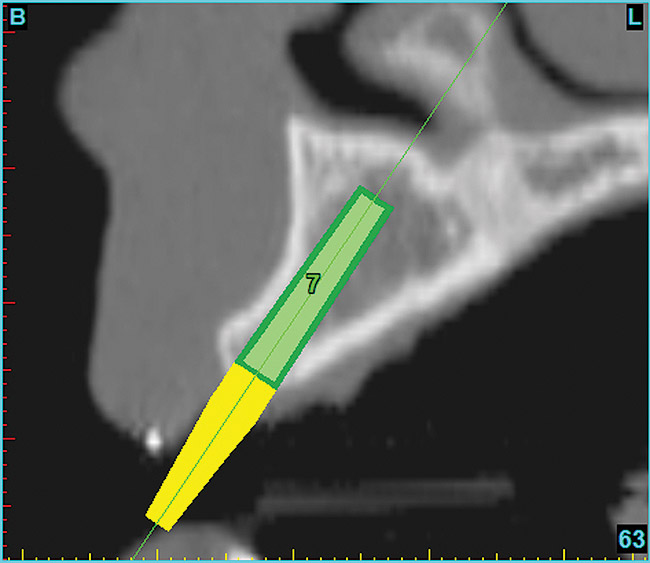

Using the interactive treatment-planning software application, the scan data was assimilated and both potential lateral incisor implant receptor sites were evaluated. It is a combination of the data and the methodology used to interpret the data that is the basis for defining a new paradigm in diagnosis and treatment planning. Proper evaluation of these images and correct use of the interactive treatment planning software tools is essential in creating a decision tree of treatment options. First, the data from the scan was reformatted into panoramic, axial, and cross-sectional images. The undistorted cross-sectional images revealed the residual alveolar bone in the area of the right lateral incisor. Then, a simulated schematic implant was placed within the bone with an abutment extension to help visualize the connection to the restorative position of the tooth (Figure 6). The Triangle of Bone® (TOB), a concept developed by the author to analyze bone quality, quantity, and disposition at prospective dental implant sites using CBCT scans, aided in determining available bone volume by defining a “zone” for proper implant placement18,19 (Figure 7).

After reviewing the CT data and the decision tree, the bone within the “zone” of the TOB was evaluated and found to be satisfactory for implant placement. Because the goal of implant dentistry is not the implant but the tooth that is placed, true restorative-driven implant dentistry must begin with the assumption that the implant position should remain consistent with the tooth it is replacing, and the final implant-supported restoration.12,22-26 The TOB aids the clinician in understanding the link between the implant position and the desired restorative goal. The base of the geometric shaped “zone” is visualized by starting at the widest area of alveolar bone facially and superiorly. The apex of the triangle is positioned to bisect the alveolar crest (Figure 7). The TOB, the overlay in the cross-sectional image, reveals whether adequate bone is available for implant placement. It also helps to identify concave facial bone defects, and accurately determine the width of bone at the crest. The author recommends using an interactive software application that provides the necessary measurement tools to accurately assess the bone anatomy.

Figure 7  SOFTWARE IMAGING The determination of the "zone" for proper placement.

Figure 7